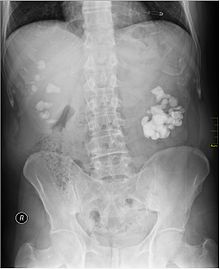

Imaging studies

Calcium-containing stones are relatively radiodense, and they can often be detected by a traditional radiograph of the abdomen that includes the kidneys, ureters, and bladder (KUB film).[28] Some 60% of all renal stones are radiopaque.[29][30] In general, calcium phosphate stones have the greatest density, followed by calcium oxalate and magnesium ammonium phosphate stones. Cystine calculi are only faintly radiodense, while uric acid stones are usually entirely radiolucent.[31]

Where available, a noncontrast helical CT scan with 5 millimeters (0.20 in) sections is the diagnostic modality of choice in the radiographic evaluation of suspected nephrolithiasis.[3][26][29][32][33] All stones are detectable on CT scans except very rare stones composed of certain drug residues in the urine,[28] such as from indinavir.

Where a CT scan is unavailable, an intravenous pyelogram may be performed to help confirm the diagnosis of urolithiasis. This involves intravenous injection of a contrast agent followed by a KUB film. Uroliths present in the kidneys, ureters or bladder may be better defined by the use of this contrast agent. Stones can also be detected by a retrograde pyelogram, where a similar contrast agent is injected directly into the distal ostium of the ureter (where the ureter terminates as it enters the bladder).[29]